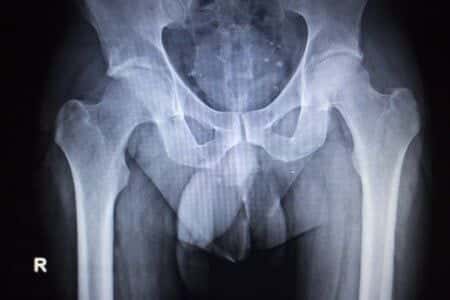

This case involves a male patient in his early sixties who underwent a total hip replacement in order to treat severe degenerative joint disease of his right hip. The patient elected to undergo a total hip replacement after conferring with an orthopedic specialist, who recommended the procedure to treat worsening pain in the joint. However, after undergoing the procedure the patient experienced a tingling sensation in his right leg, as well as foot drop. It was alleged that the operating surgeon damaged the nerves in the patient’s right leg during the hip replacement procedure.